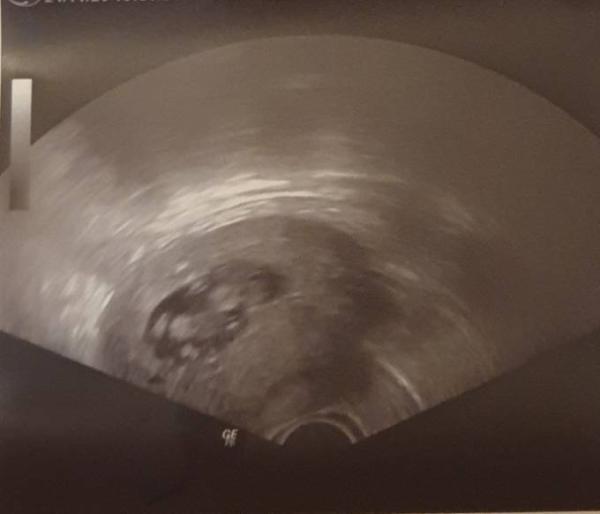

Hallo ihr Lieben, heute war der 2. Ultraschall bei mir. Dem Kleinen geht es prima, es sah aus wie ein Gummibärchen und hat sogar "getanzt" bzw ordentlich mit dem Popo gewackelt . Ein wunderschöner Anblick Anbei ein Bild. Ich bin so glücklich!!!

Bild zu 2. Kontrolluntersuchung - Forum für Juni - Mamis